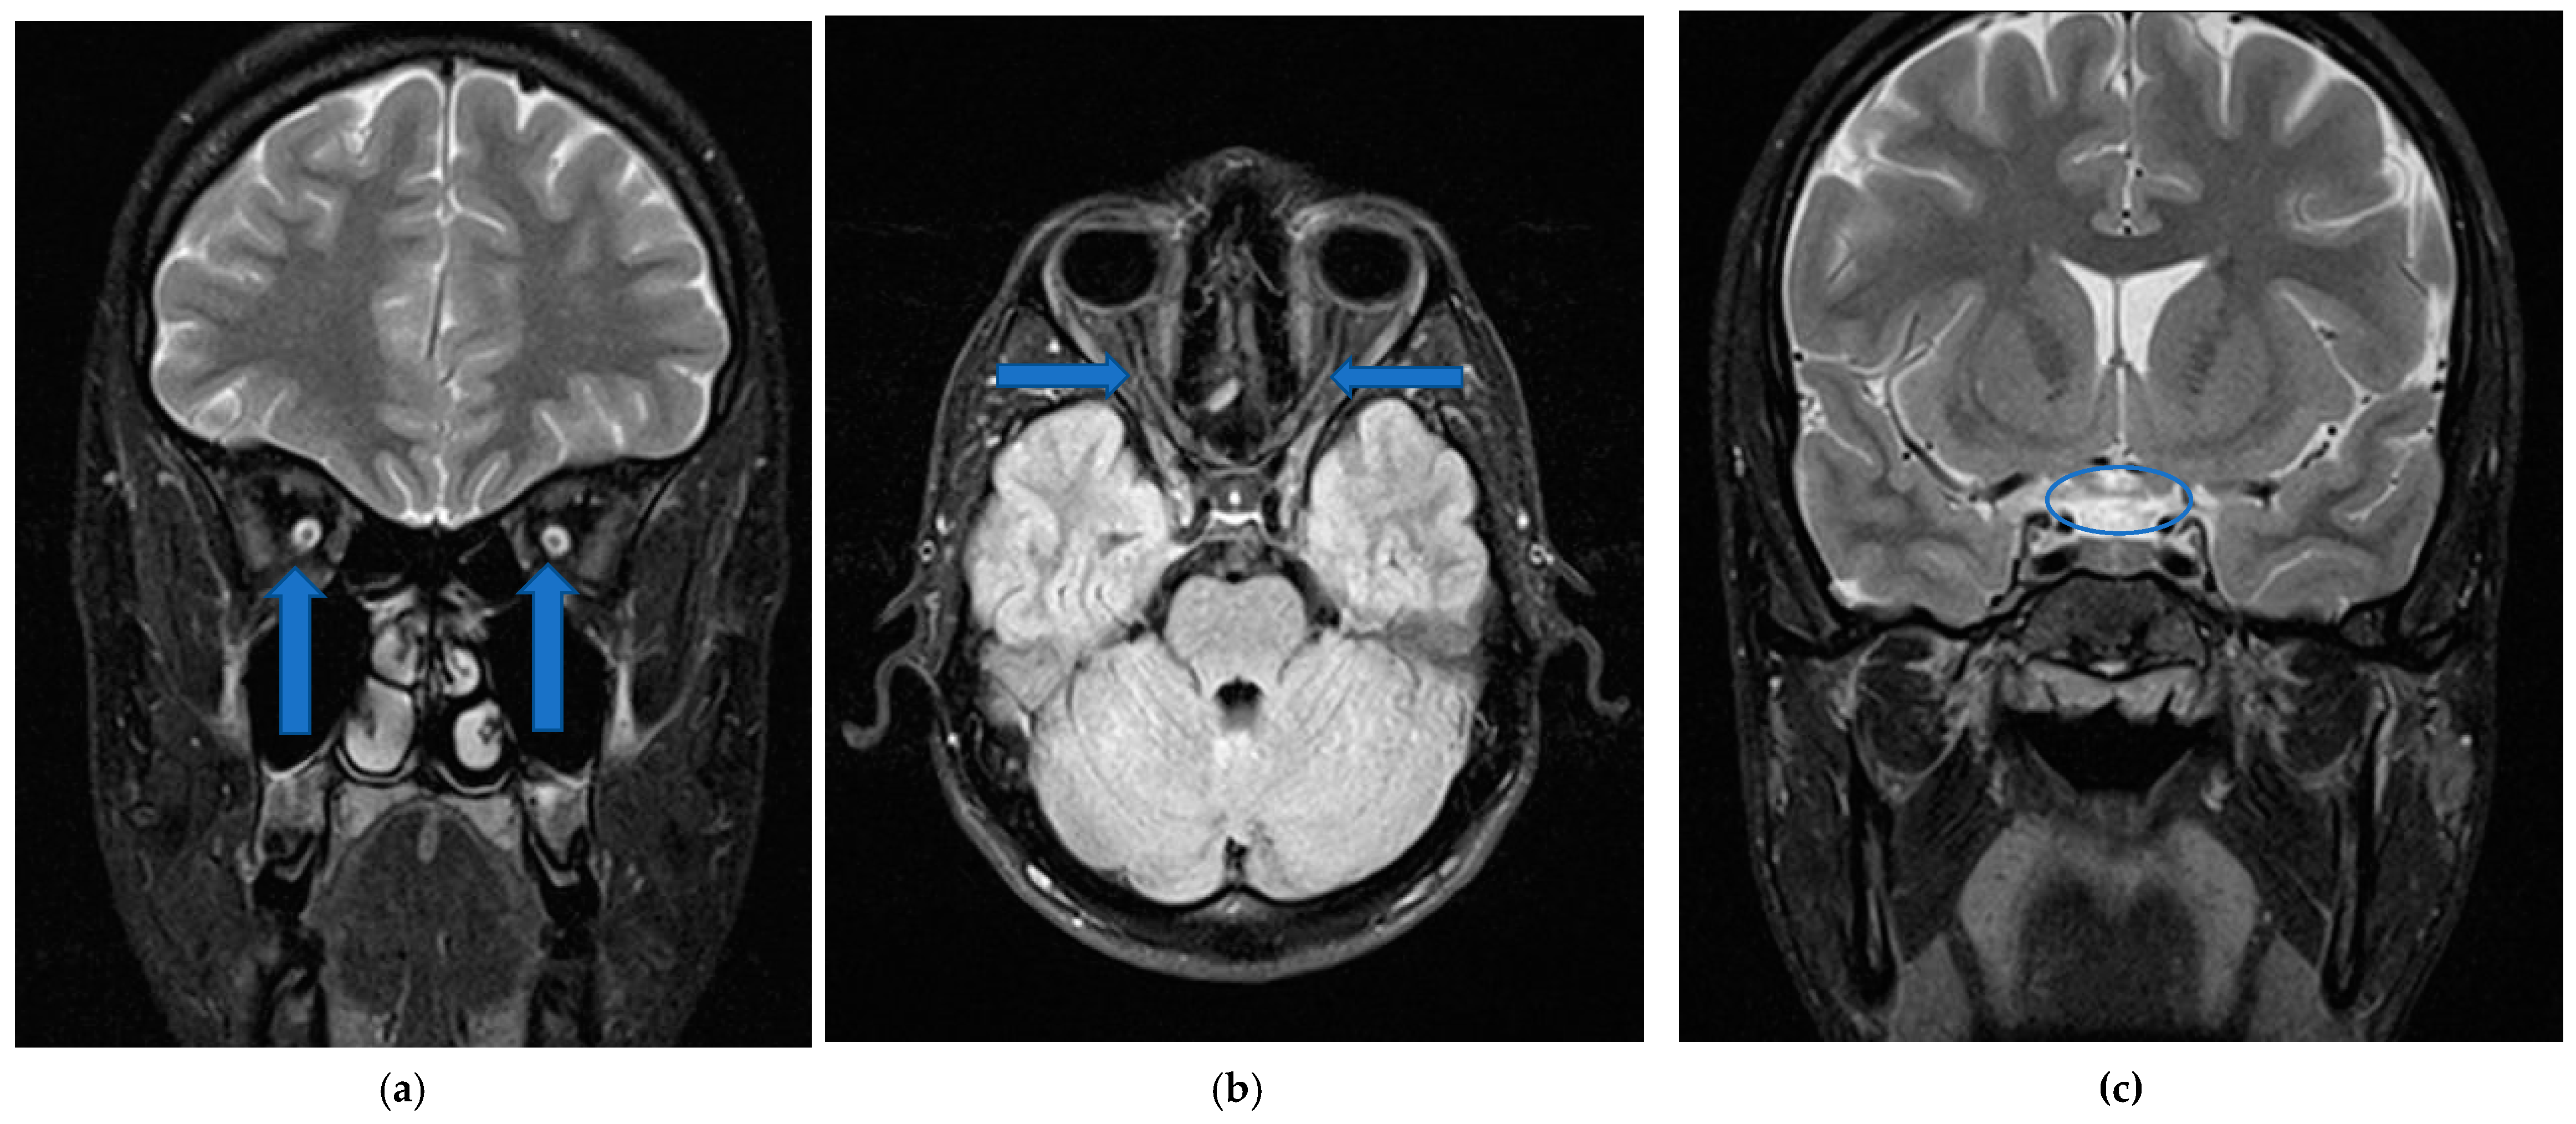

7. Case Report